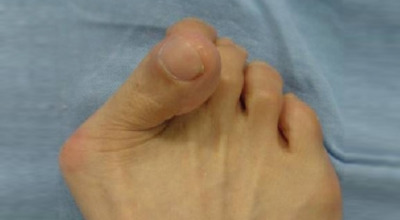

무지외반증이 진행되면 육안으로 엄지발가락의 변형이 뚜렷하게 나타납니다. 초기에는 굳은살이 생기고 약간의 통증이 동반될 수 있습니다. 엄지발가락이 돌출된 부위는 신발에 자극을 받아 두꺼워지고 염증이 발생하여 통증이 생깁니다. 발바닥이 휘어지지 않더라도 굳은살 때문에 정상적인 보행이 어려워지고, 심한 경우에는 통증으로 인해 신발을 신는 것조차 힘들어질 수 있습니다. 증상이 계속 악화되면 엄지발가락이 겹쳐지거나 탈구되는 경우도 발생할 수 있습니다.

또한, 엄지발가락이 옆으로 휘어지면서 관절에 비정상적인 압력이 가해져 퇴행성 관절염이 생길 수 있습니다. 엄지발가락이 발바닥의 압력을 지지하지 못하게 되면, 2, 3번째 발가락으로 그 부담이 옮겨져 발바닥에 굳은살이 생기고, 발가락 뼈 사이의 신경이 부풀어 통증을 일으키는 지간신경종이 발생할 수 있습니다.